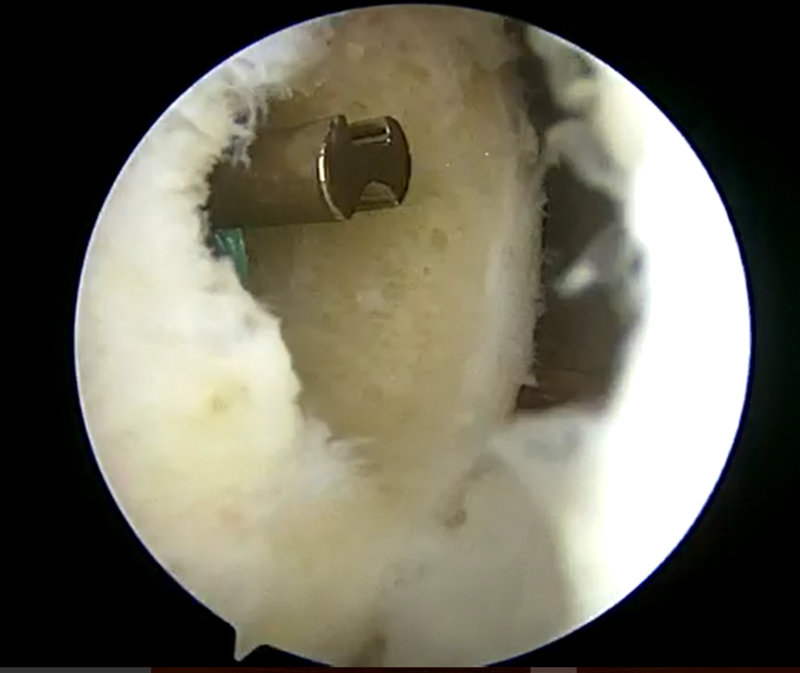

![]() |

| 前十字靭帯損傷部 | 大腿骨側骨孔作成 | 脛骨骨孔作成 |